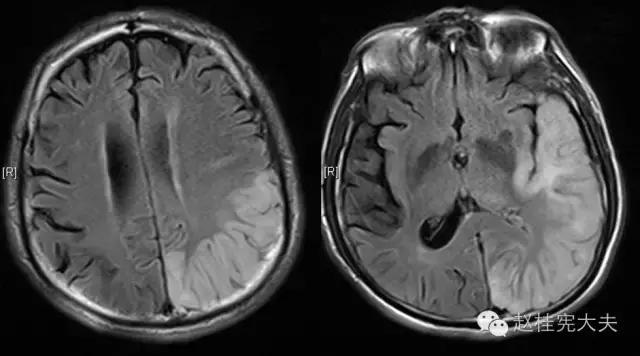

上周,于发病后2月复查磁共振:

到此为止,MELAS的诊断应该在没有基因确诊的情况下在临床上得到认可了,患者明确诊断为线粒体脑肌病伴乳酸血症和卒中样发作(MELAS),解释了患者的所有症状,患者母亲不明原因地死亡也得以真相大白,患者的相关亲属们在未来的人生路上也多了一份呵护......